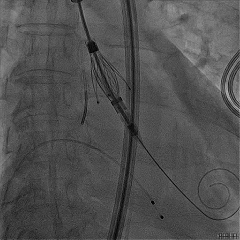

定位键解离

推送入窦形态改变不明显

无窦瓣叶脱垂影响瓣叶夹持

回撤后增加调弯夹持瓣叶

右窦中心造影确认瓣叶夹持

食道超声确认瓣叶夹持

经胸超声确认右冠瓣叶夹持